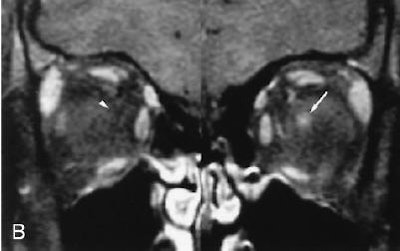

| Seventeen-year-old girl with moderate imaging findings of optic neuropathy due to cat scratch fever. Axial (A) and coronal (B) gadolinium-enhanced, fat-suppressed, T1-weighted images (TR1, Tr2/TE, 735, 875/14) show bulging of the left optic disk (arrow in A) that is markedly less pronounced than that on the right (arrowhead in A). The associated enhancement at the left optic nerve-globe junction (arrow in A and B) is also markedly less extensive. Note that normal appearance of the optic nerve-globe junction region on the right (arrowhead in A and B). Schmalfuss IM, Dean CW, Sistrom C, Bhatti MT, "Optic Neuropathy Secondary to Cat Scratch Disease: Distinguishing MR Imaging Features from Other Types of Optic Neuropathies" (AJNR, 26:1310-1316, June/July 2005). |